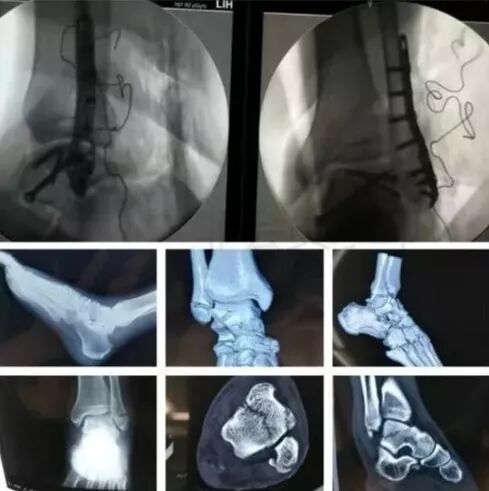

7)胫骨远端(pilon,踝部)

图片

• pilon骨折,高能损伤,6-8h肿胀未形成,可以急诊做,手术时间<3小时。

• 10-14天,分步延期手术策略。

• 踝部骨折手术时机同样取决于皮肤条件。

8)足部骨折(距骨,跟骨,跖骨等)

高能损伤导致的距骨骨折并脱位,建议急诊做。